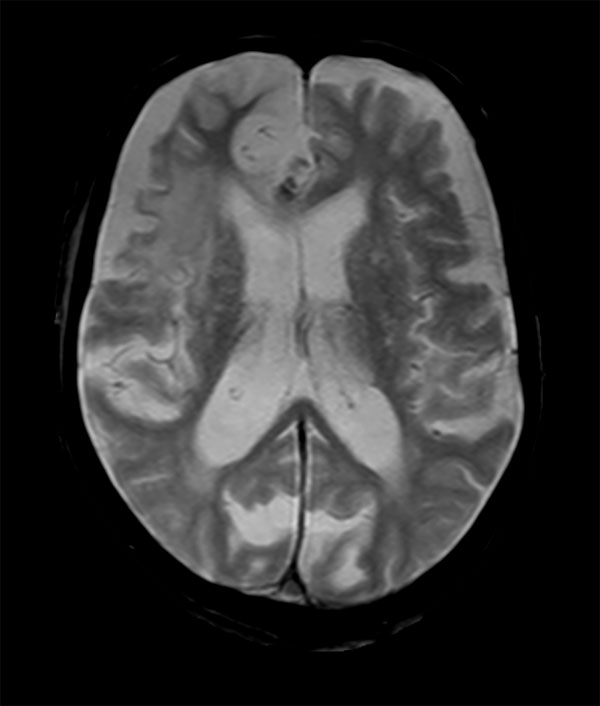

Acute stroke. Patient was brought to the first aid and directly transferred to the MRI unit. Axial studies were performed to get an overview of the stroke. Total study time is 9 minutes.

Axial T2w TSE

Axial T2* FFE